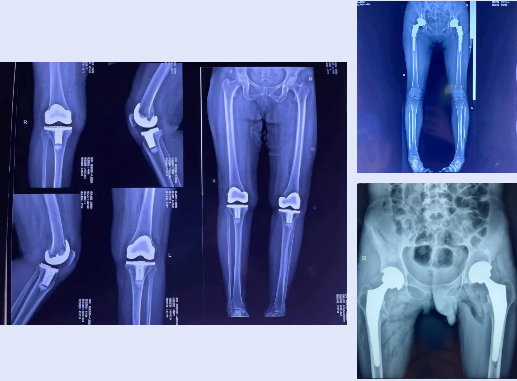

此9例患者年龄跨度较大,身体状况不一,均为疑难复杂病例,为保障手术顺利进行,经全科术前讨论,积极准备后,决定为患者分别行人工全髋关节置换术、微创前路全髋关节置换术,双髋关节僵直畸形关节置换术、严重膝关节屈曲内翻畸形人工全膝关节置换术。手术在手术麻醉科副主任张建荣、张岁林亲自把关下均顺利完成,术后疗效显著,缩短了患者的住院周期,减轻了患者经济负担,受到了患者及家属的一致好评。

▲术后影像资料

尤其是一位年仅20岁强直性脊柱炎继发重度双髋骨关节炎伴关节僵直畸形患者,因他长期无法就坐,只能常年站立,严重影响基本生活,荒废学业。辍学后曾在全国各大医院就诊、治疗,症状有所缓解,但未根除。近日因病情复发,遂来我院骨三科就诊。入院后,骨三科主任杨小广和主治医师邵誉亮组织全科医师讨论,决定邀请华西专家远程会诊,会诊后将治疗方案通知家属和本人,患者同意我院和华西专家共同完成手术。术后仅仅1天,患者髋关节可以开始主动活动。